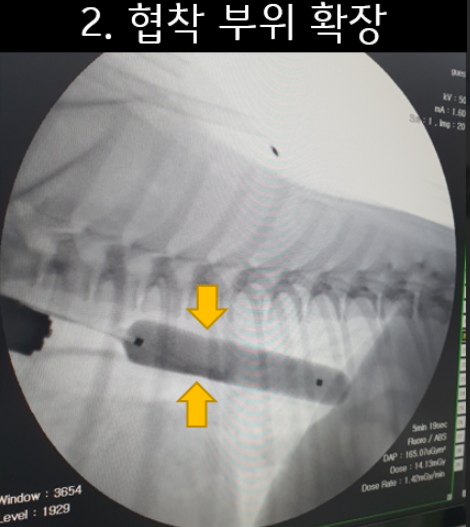

환자 식도의 상태와 크기 등을 고려 하여 ‘Balloon을 이용한 식도 확장술’을 결정하였습니다.

‘Balloon을 이용하는 식도확장술’은 환자 크기에 맞는 다양한 크기의 Balloon 장비들과 크기를 조절할 수 있는 압력계, 내시경과 C-arm 장비가 필요합니다.

환자는 2kg대이기에 식도의 크기에 맞은 Balloon을 확보 후 총 3회에 걸쳐 확장술을 진행하였습니다.

1차 확장 시에는 환자의 식도가 6mm에서 1mm 단위로 12mm 까지 확장을 진행하였습니다.